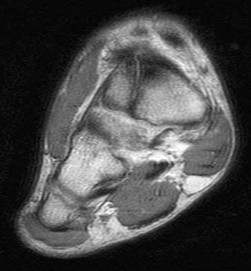

A 55-year-old woman feels a 'pop' in the back of her knee while squatting. An MRI is shown:

A posterior horn medial meniscus root tear is identified. Biomechanically, a complete medial meniscus posterior root tear alters contact pressures to a degree equivalent to which of the following?

Explanation

A complete posterior root tear of the medial meniscus leads to a complete loss of hoop stresses, resulting in meniscal extrusion. Biomechanically, this alters peak tibiofemoral contact pressures and reduces contact area to a degree equivalent to a total meniscectomy, leading to rapid articular cartilage degeneration.